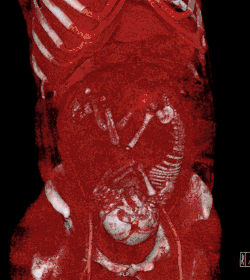

CT scanning (volume rendered in this case) confers a radiation dose to the developing fetus.

Medical imaging may be indicated in pregnancy because of pregnancy complications, a pre-existing disease or an acquired disease in pregnancy, or routine prenatal care. Magnetic resonance imaging (MRI) without MRI contrast agents as well as obstetric ultrasonography are not associated with any risk for the mother or the fetus, and are the imaging techniques of choice for pregnant women.[39] Projectional radiography, CT scan and nuclear medicine imaging result some degree of ionizing radiation exposure, but have with a few exceptions much lower absorbed doses than what are associated with fetal harm.[39] At higher dosages, effects can include miscarriage, birth defects and intellectual disability.[39]